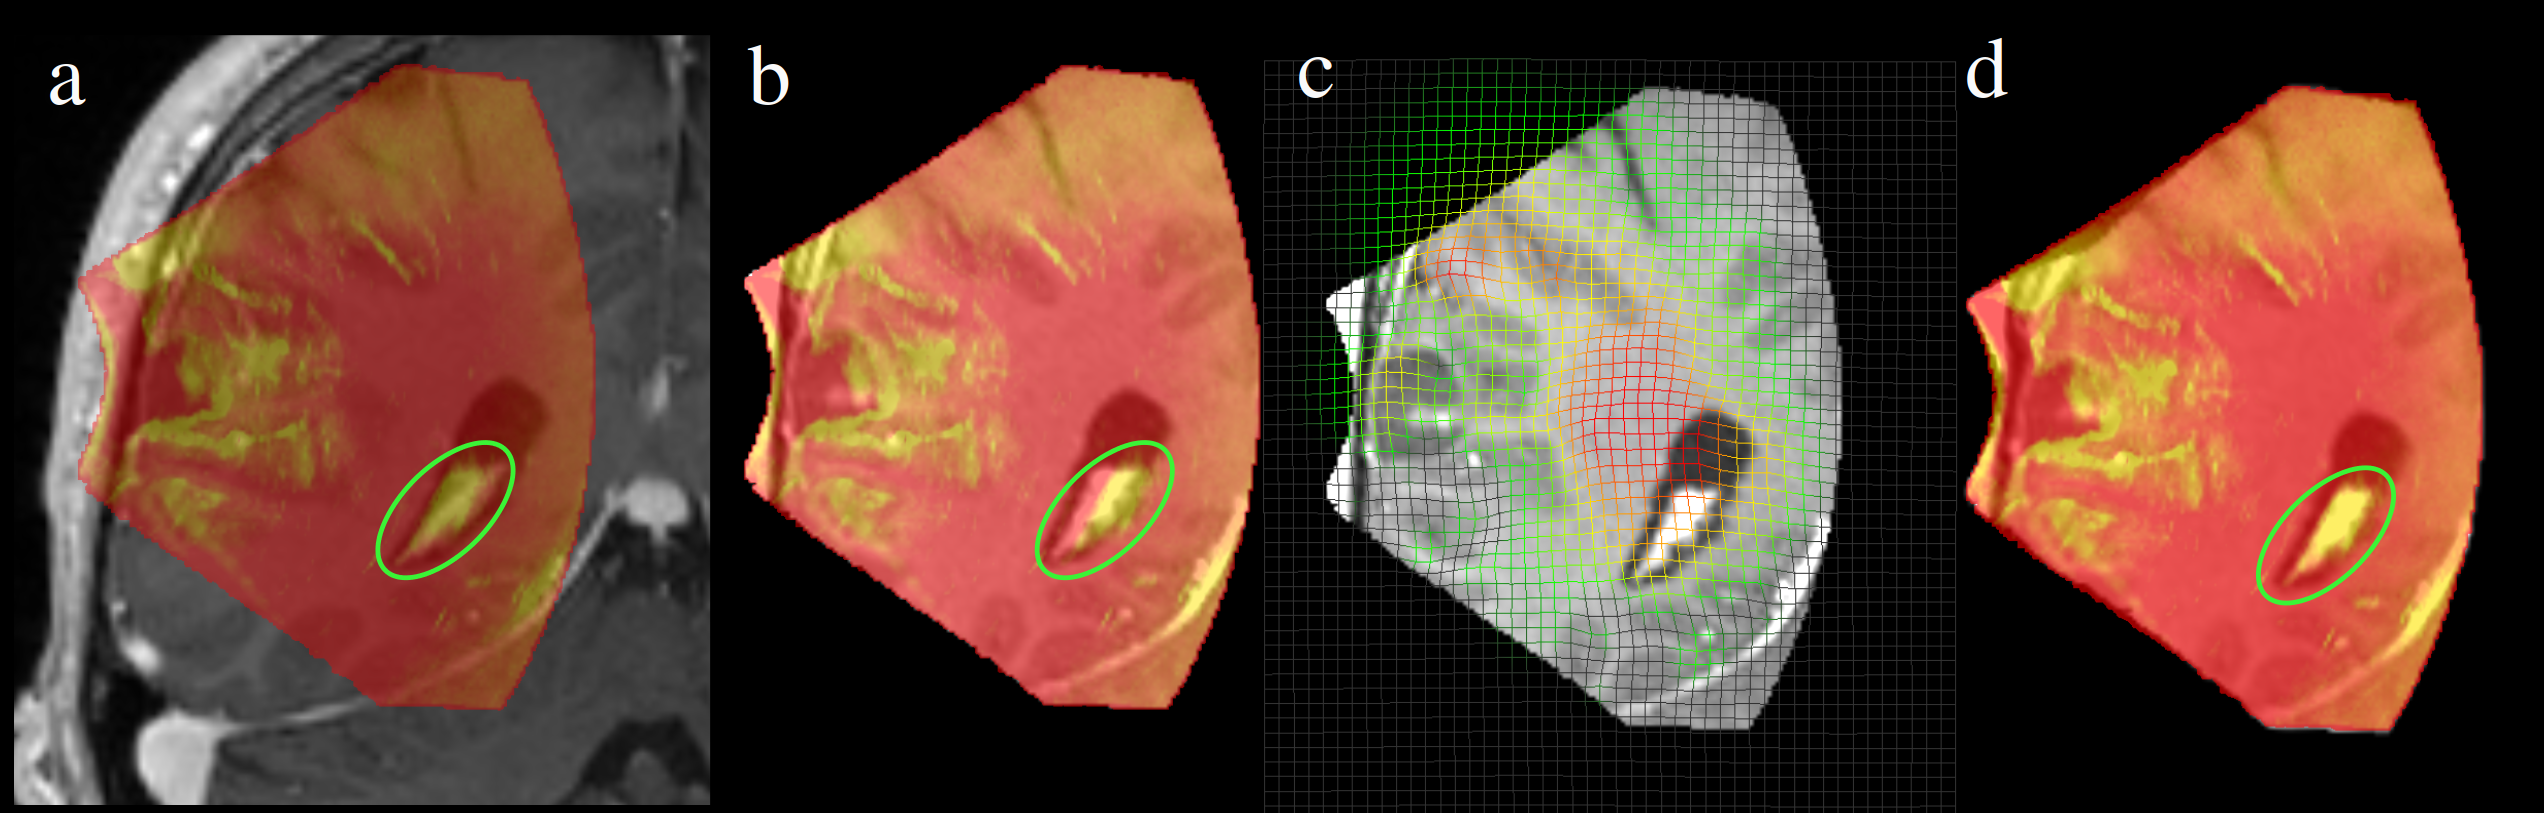

However, this metric shows inadequate consistency with the Target Registration Error (TRE). In some cases, a decrease in the MSE of SSC does not correspond to a similar reduction in TRE. Although the SynthMorph shows more consistency with fixed US image in the circled area, as depicted in Fig. 5, the TRE rises from 1.60 mm to 2.38 mm.

Refer to caption

Figure 5: The visualization of the deformation field, and the overlap of fixed US image and MR images after different stages. a) The difference of original MR image with US image, b) The difference of MR image after an affine alignment and US image c) deformable field applied on MR image d) The difference of final MR image and US image.